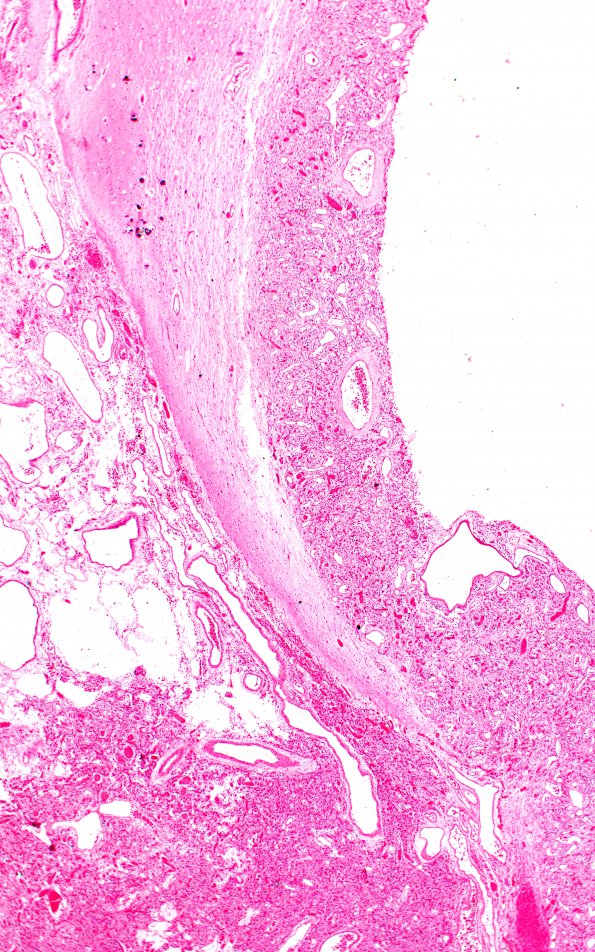

Washington University Experience | NEOPLASMS (MESENCHYMAL, NON-MENINGOTHELIAL) | Hemangioblastoma | 10A6 (Case 10) H&E f 2X

10A6,7 Higher magnification of the tumor within the 3rd ventricle shows a routine hemangioblastoma consisting of numerous capillary-sized vessels interspersed with nests of stromal cells with foamy cytoplasm. The nuclei of many of the tumor cells show a moderate to marked degree of pleomorphism and hyperchromaticity, and scattered giant tumor cells are seen. However, no mitoses were identified